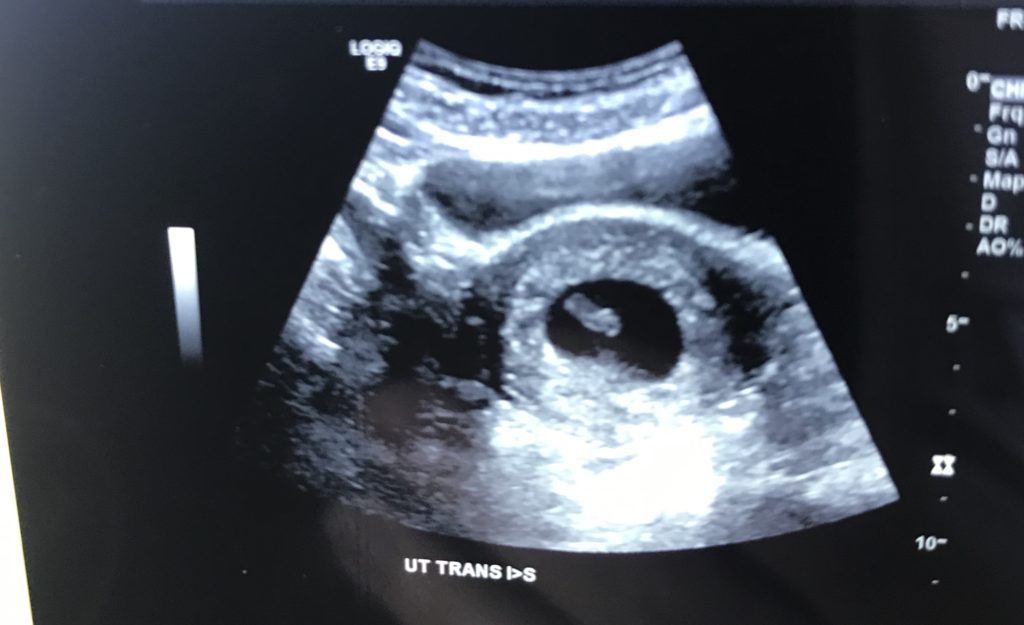

It is more common that the first ultrasound is done trans-vaginally at this early stage of pregnancy. The technician will insert a vaginal wand transmitter inside your vagina, and then she will maneuver it from there to take measurements and other important data. A transvaginal ultrasound is done to get the best look at the baby. This part of the test does not hurt. It may feel a little strange and uncomfortable, but you shouldn’t feel pain. If anything hurts or doesn’t feel alright, express this to the technician. She may be trying to get the different view and it’s putting pressure on your ovaries or other areas.

Unless you are receiving an emergent scan done at the hospital, you will most likely receive an image of your baby at this first ultrasound. Ask your technician before she is done scanning you to make sure they will print it out for you. Ultrasound scans are cherished memories that will last a lifetime, and you may use your scans for keepsakes, digital pregnancy announcements, and to place in your baby book!